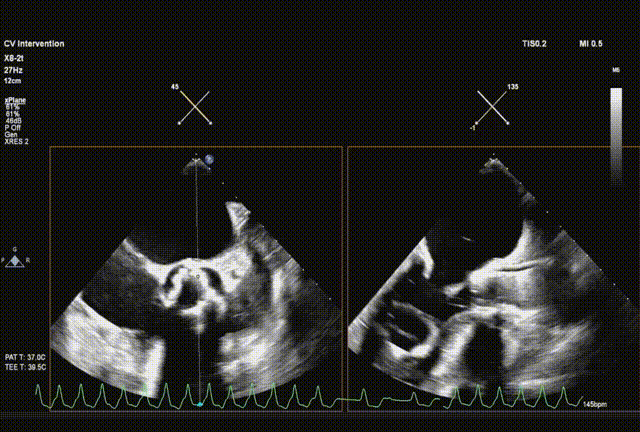

采样线扫到无窦,180起搏,长轴视图下快速释放到工作位

超声从左至右,最后无冠窦侧评估深度合适

起搏下完全释放瓣膜

左右旋转系统并前送,观察无瓣膜移动,回撤导丝后再撤出系统

术后超声评估,未见瓣周漏,平均跨瓣压15 mmHg,血流速度197 cm/s